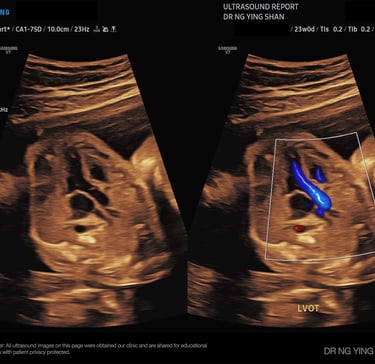

18-22

weeks

Detailed / Anomaly Scan

Looks closely at the baby’s organs, spine, heart, limbs, placenta, and amniotic fluid to check that everything is developing well.